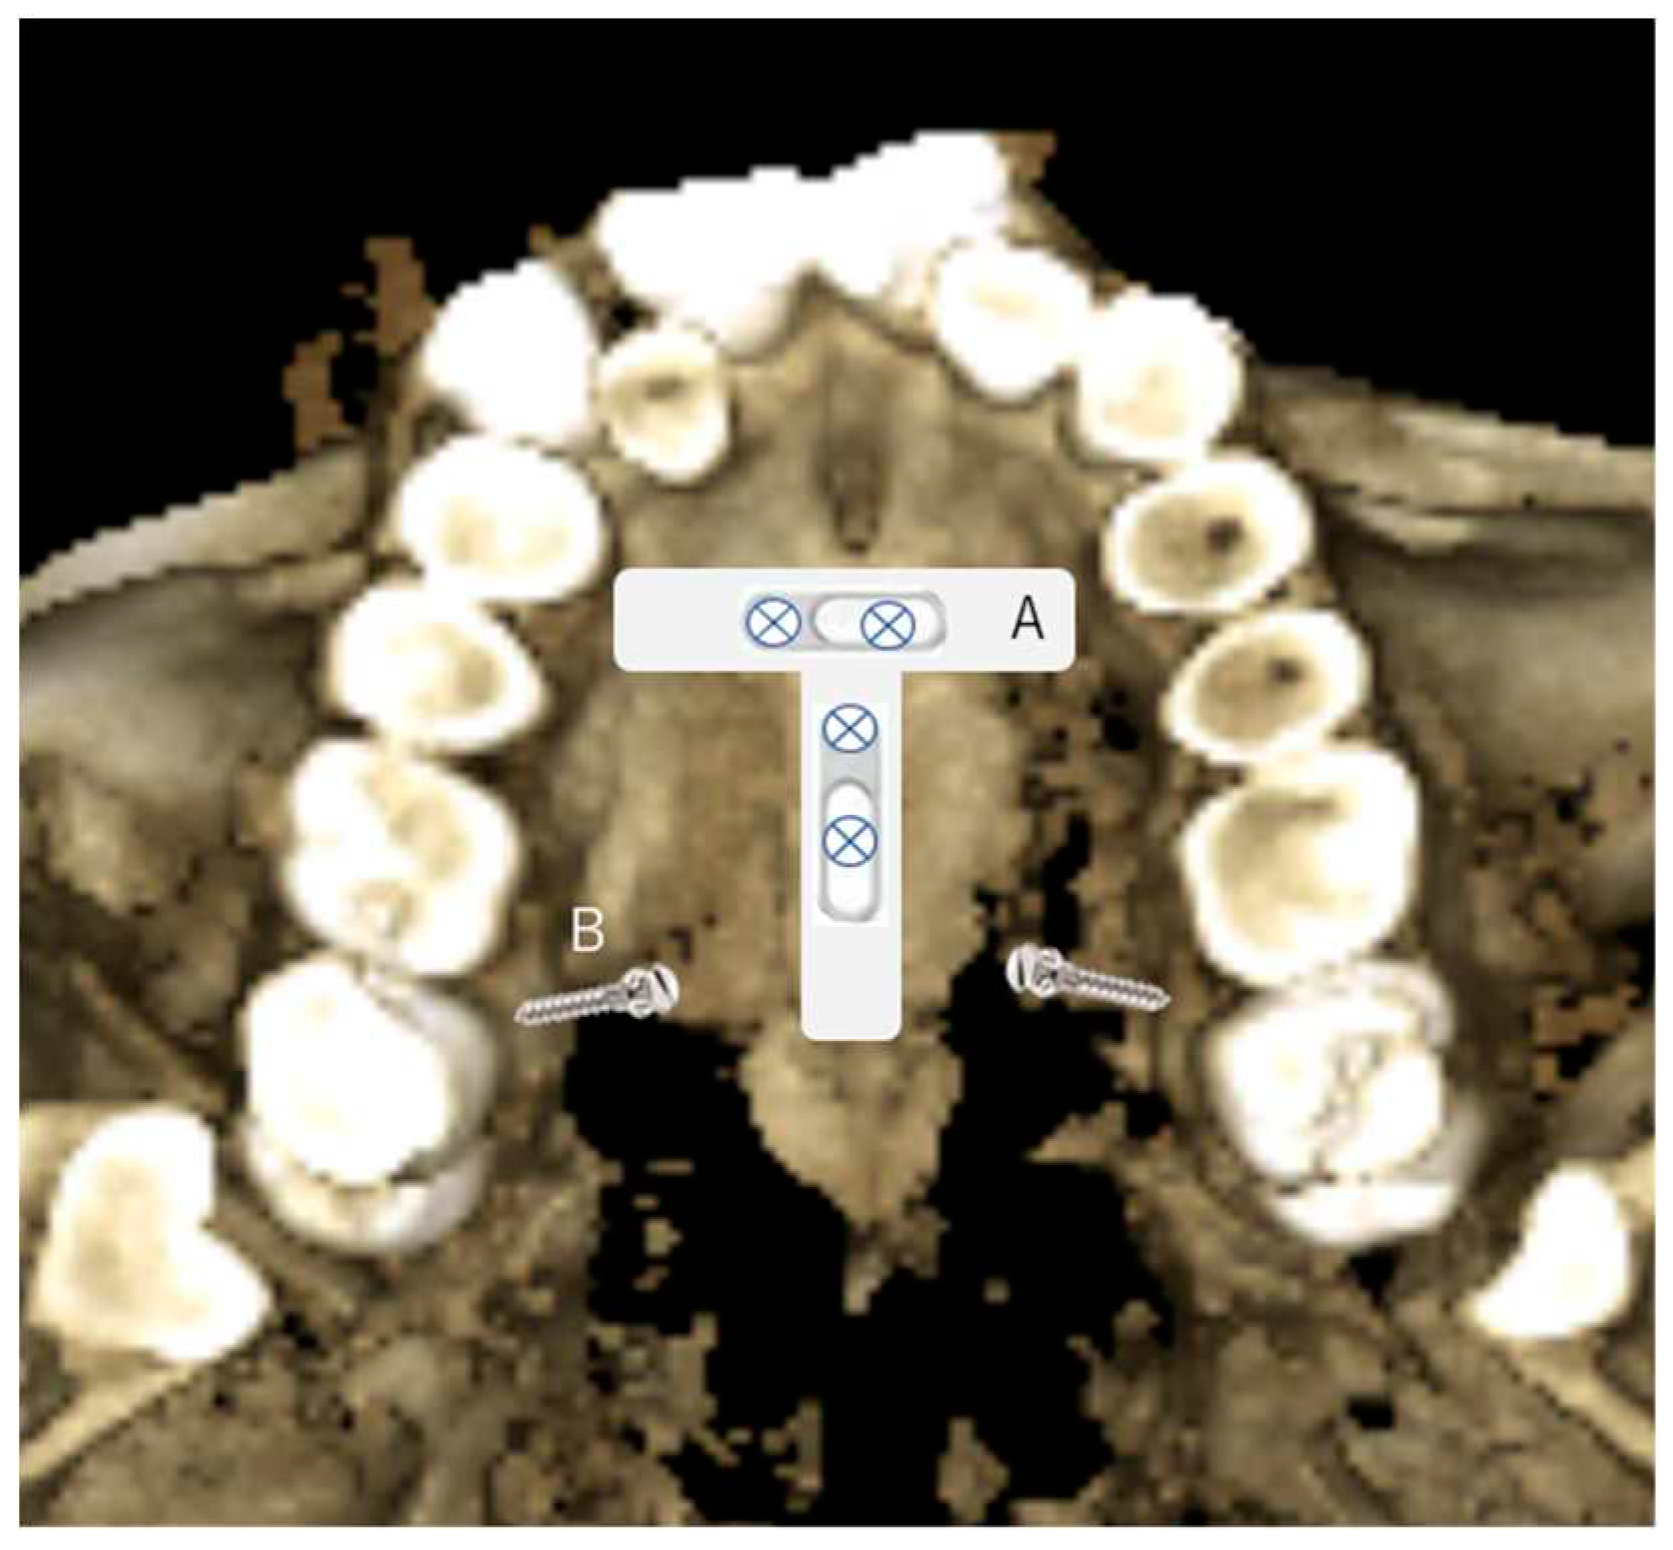

- In the maxilla, use CBCT to look for the ideal places and the palatal sites in the T-zone, as described by Wilmes (26). The Benefit’s system is two screws being used to connect a plate to make it a sturdy anchorage for a 3D movement of the upper teeth. Therefore, the two screws’ placement is critical to insert the plate easily and quickly, such as paralleling or close to the parallel to provide easy fixation. The surgical guide will facilitate the parallel insertion of TADS. TADS are placed at the best bone density in the area intended to be the anchorage placement. The other option for the TADs site in the palatal bone is between the first molar and the second bicuspid area, and the first molar has only a single palatal root (two roots on buccal) and the second bicuspid's root, which may as well be single in some clinical situations. The placement on the buccal side can also be done with the surgical guide in the anterior teeth between the central and lateral teeth for the buccal area of interdental of the bicuspids and the buccal ridge underneath the Zygomatic process.